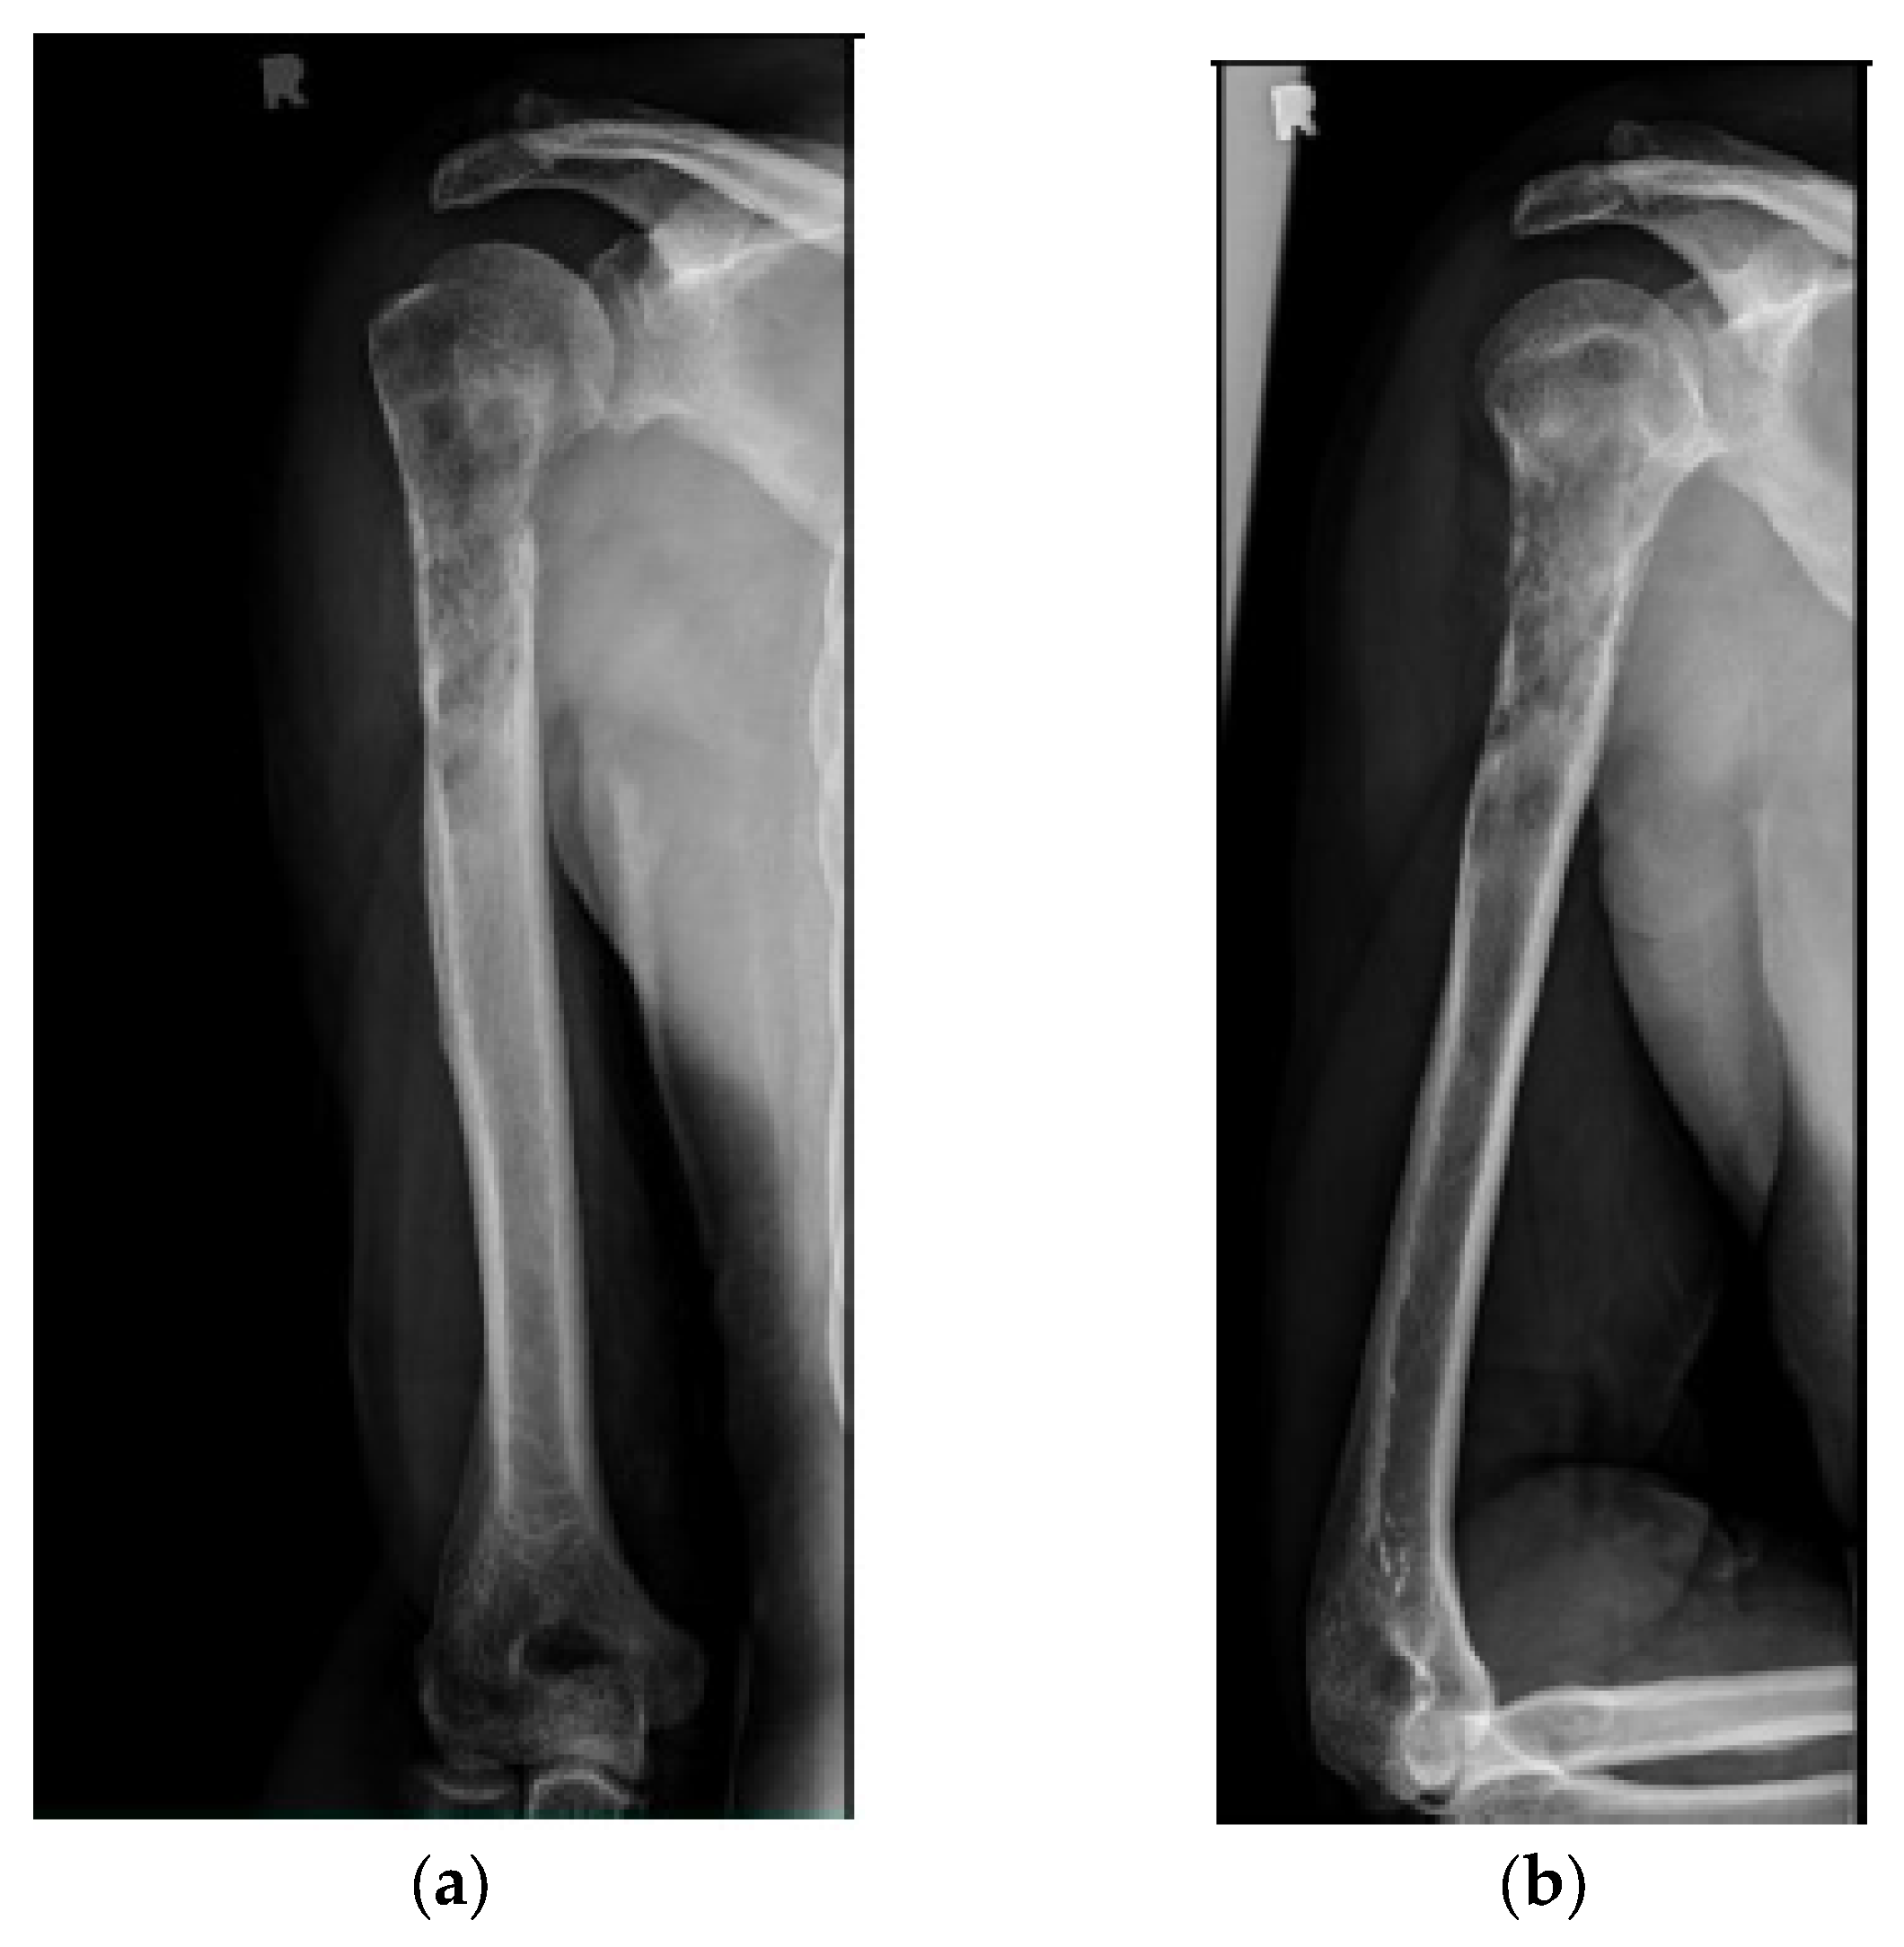

Figure 2.

(a) AP and (b) lateral right humerus radiographs of a 67-year-old male with a mixed lytic sclerotic lesion in the proximal meta-diaphyseal region, with a pathologic fracture from a newly diagnosed metastatic prostate cancer. This was treated by a bone biopsy, followed by a cemented IMN with two proximal inter-locking screws and no distal screw, as shown in the (c) AP and (d) lateral humerus radiographs. Cement was used for augmentation, due to poor proximal humerus bone quality, to support the nail and the inter-locking screws.

Figure 3.

(a) AP and (b) oblique left humerus radiographs of a 47-year-old female with mixed lytic sclerotic lesion in the proximal meta-diaphyseal region, with a pathologic fracture and periosteal reaction in a patient with established metastatic breast cancer. This was treated by an uncemented IMN, with three proximal locking screws and one distal screw, as shown in (c) AP and (d) oblique humerus radiographs. No cement was used, as there was enough proximal and distal bone to support the nail and the inter-locking screws, and some healing changes were already evident.